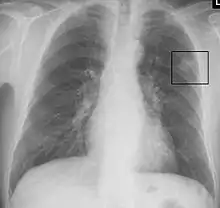

تمام انواع دخانیات انسان را در مسیر ابتلا به سرطان قرار میدهند. ترک دخانیات بهترین کار برای جلوگیری از سرطان در این افراد است. خودداری از مصرف دخانیات از خطر چندین نوع سرطان میکاهد از جمله: ریه، مری، حنجره، دهان، مثانه، کلیهها، لوزالمعده، گردن رحم، سرطان خون (لوسمی میلویید حاد).[5]

در ایالات متحده آمریکا سیگار مسئول حدود ۹۰ درصد تمام موارد سرطان ریه که یک علت عمده مرگهای ناشی از سرطان در مردان و زنان است بهشمار میرود. با هر بار استعمال سیگار، بیشتر از ۶۰ ماده سرطان زا وارد ریه هامی شود. به علاوه تار (ماده قیر مانند) موجود در دود سیگار لایه قهوهای رنگ چسبندهای را بر روی پوشش داخل حبابهای هوایی و مسیرهای عبور هوا میسازد که خود مقدار زیادی از این مواد سرطانزا در خود نگه میدارد. فرودادن دود سیگار یا جویدن و تف کردن توتون هیچکدام سالم و بدون خطر نیستند. سیگاریها، در مقایسه با غیرسیگاریها بیشتر دچار سرطان ریه و نیز سرطان حنجره، مری و دهان میشوند. جویدن توتون همچنین بر خطر ابتلا به سرطانهای دهان، گونهها و لثه میافزاید. حتی اگر خودتان سیگار نمیکشید، خود را در معرض دود دیگران قرار ندهید. همه ساله حدود ۳۰۰۰ غیر سیگاری در نتیجه قرار گرفتن در معرض دود از سرطان ریه میمیرند.[9][10] دود سیگار حاوی بیش از ۶۰ ماده سرطانزا شناخته شدهاست.[11][12] مانند ایزوتوپ پرتوزا ناشی از فرایند تجزیه رادون. همچنین، نیکوتین پاسخ ایمنی بدن را در مقابل رشد سلولهای سرطانی در بافتهای آسیب دیده سرکوب میکند.[13]